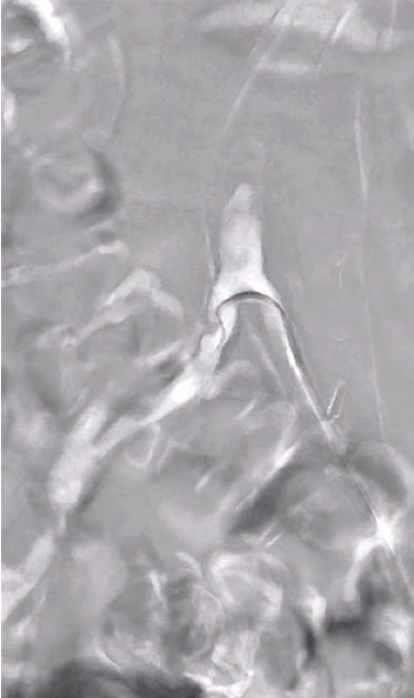

Roadmap imaging represents a sophisticated blend of pre-acquired images (often from computed tomography [CT] angiography or DSA) with real-time fluoroscopy, providing a continuous overlay that allows for precise guidance throughout the procedure. The technology works by creating a “virtual road” overlaid onto live fluoroscopic images, facilitating catheter and device navigation.

1. Enhanced Precision in Complex Anatomy: The ability to superimpose pre-acquired images over real-time fluoroscopy improves the visualization of vessel course, tortuosity, and calcifications, essential for navigating complex below-knee vessels.

4. Real-Time Guidance: The fusion of live fluoroscopy with static images allows for immediate, real-time adjustments in catheter and wire placement, improving procedural outcomes and efficiency. This is particularly beneficial in below-knee interventions, where vessel access and navigation can be particularly challenging due to tortuosity, small vessel calibers, and collateral circulation.

1. Tortuosity and Calcifications: Roadmap imaging allows for accurate identification and navigation around tortuous or calcified segments, which is crucial for reducing the risk of procedural failure or complications, such as arterial perforation or dissection.